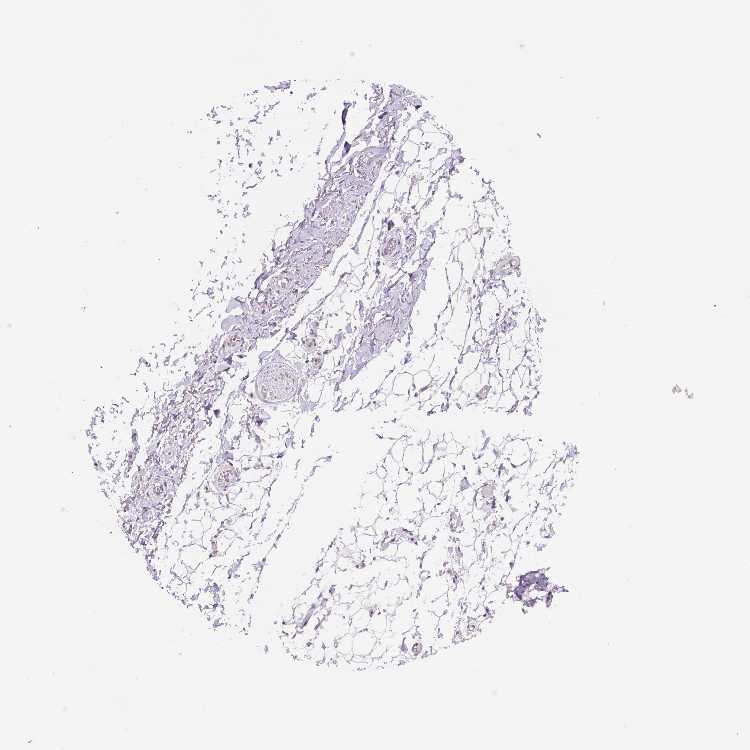

SOFT TISSUE 2 - Antibody stainingi

Antibody staining in the annotated cell types in the current human tissue is reported as not detected, low, medium, or high, based on conventional immunohistochemistry profiling in selected tissues. This score is based on the combination of the staining intensity and fraction of stained cells.

Each image is clickable and will lead to virtual microscopy that enables deeper exploration of all samples and also displays staining intensity scores, fraction scores and subcellular localization as well as patient and tissue information for each sample.

Antibody CAB070417

Fibroblasts Not detected

Peripheral nerve Not detected